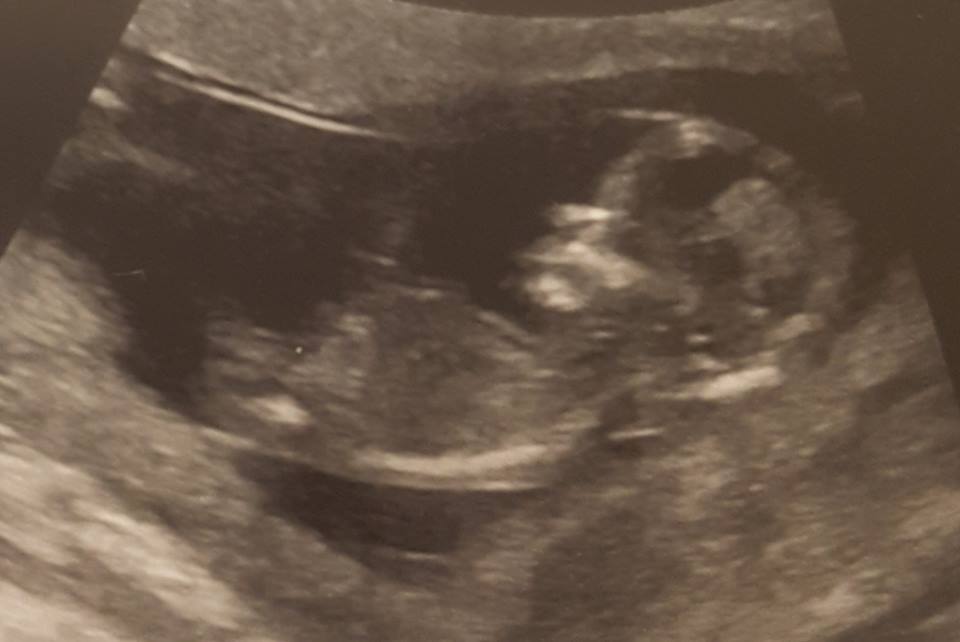

13w2d:

Attachment 36545